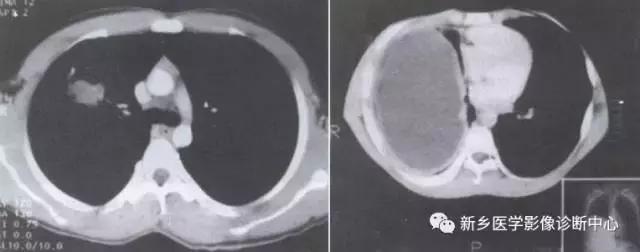

单发肺转移瘤

有原发肿瘤病史,多发于肺下叶。圆形密度增高影,密度常较均匀,边缘清楚,常呈分叶,无毛刺,可见强化。

下为前列腺癌转移:

下为骨肉瘤转移:

炎性假瘤

常有胸痛,咳嗽,发热,咳血。孤立类圆形肿块,密度均匀,边界清楚,少数可有斑点样钙化,抗炎治疗可缩小消失。

桃尖征,平直征:

单发胸膜间皮瘤

常发于胸壁腋缘,单发、多发良性,无症状或局部钝疼。圆形或半球形密度影,基底位于胸膜,与胸壁成钝角,密度均匀。

4个不同的胸膜间皮瘤: